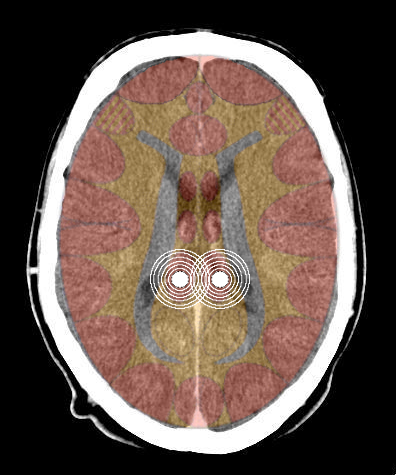

- Requisiti: Si è in costellazione schizofrenica quando due attivazioni colpiscono i due emisferi cerebrali di uno stesso livello:

- le due emiparti del tronco cerebrale;

- i due emisferi cerebellari;

- i due emisferi cerebrali (midollo e/o corteccia).

- Relè cerebrali: Due SBS (uno in ogni emitronco cerebrale);